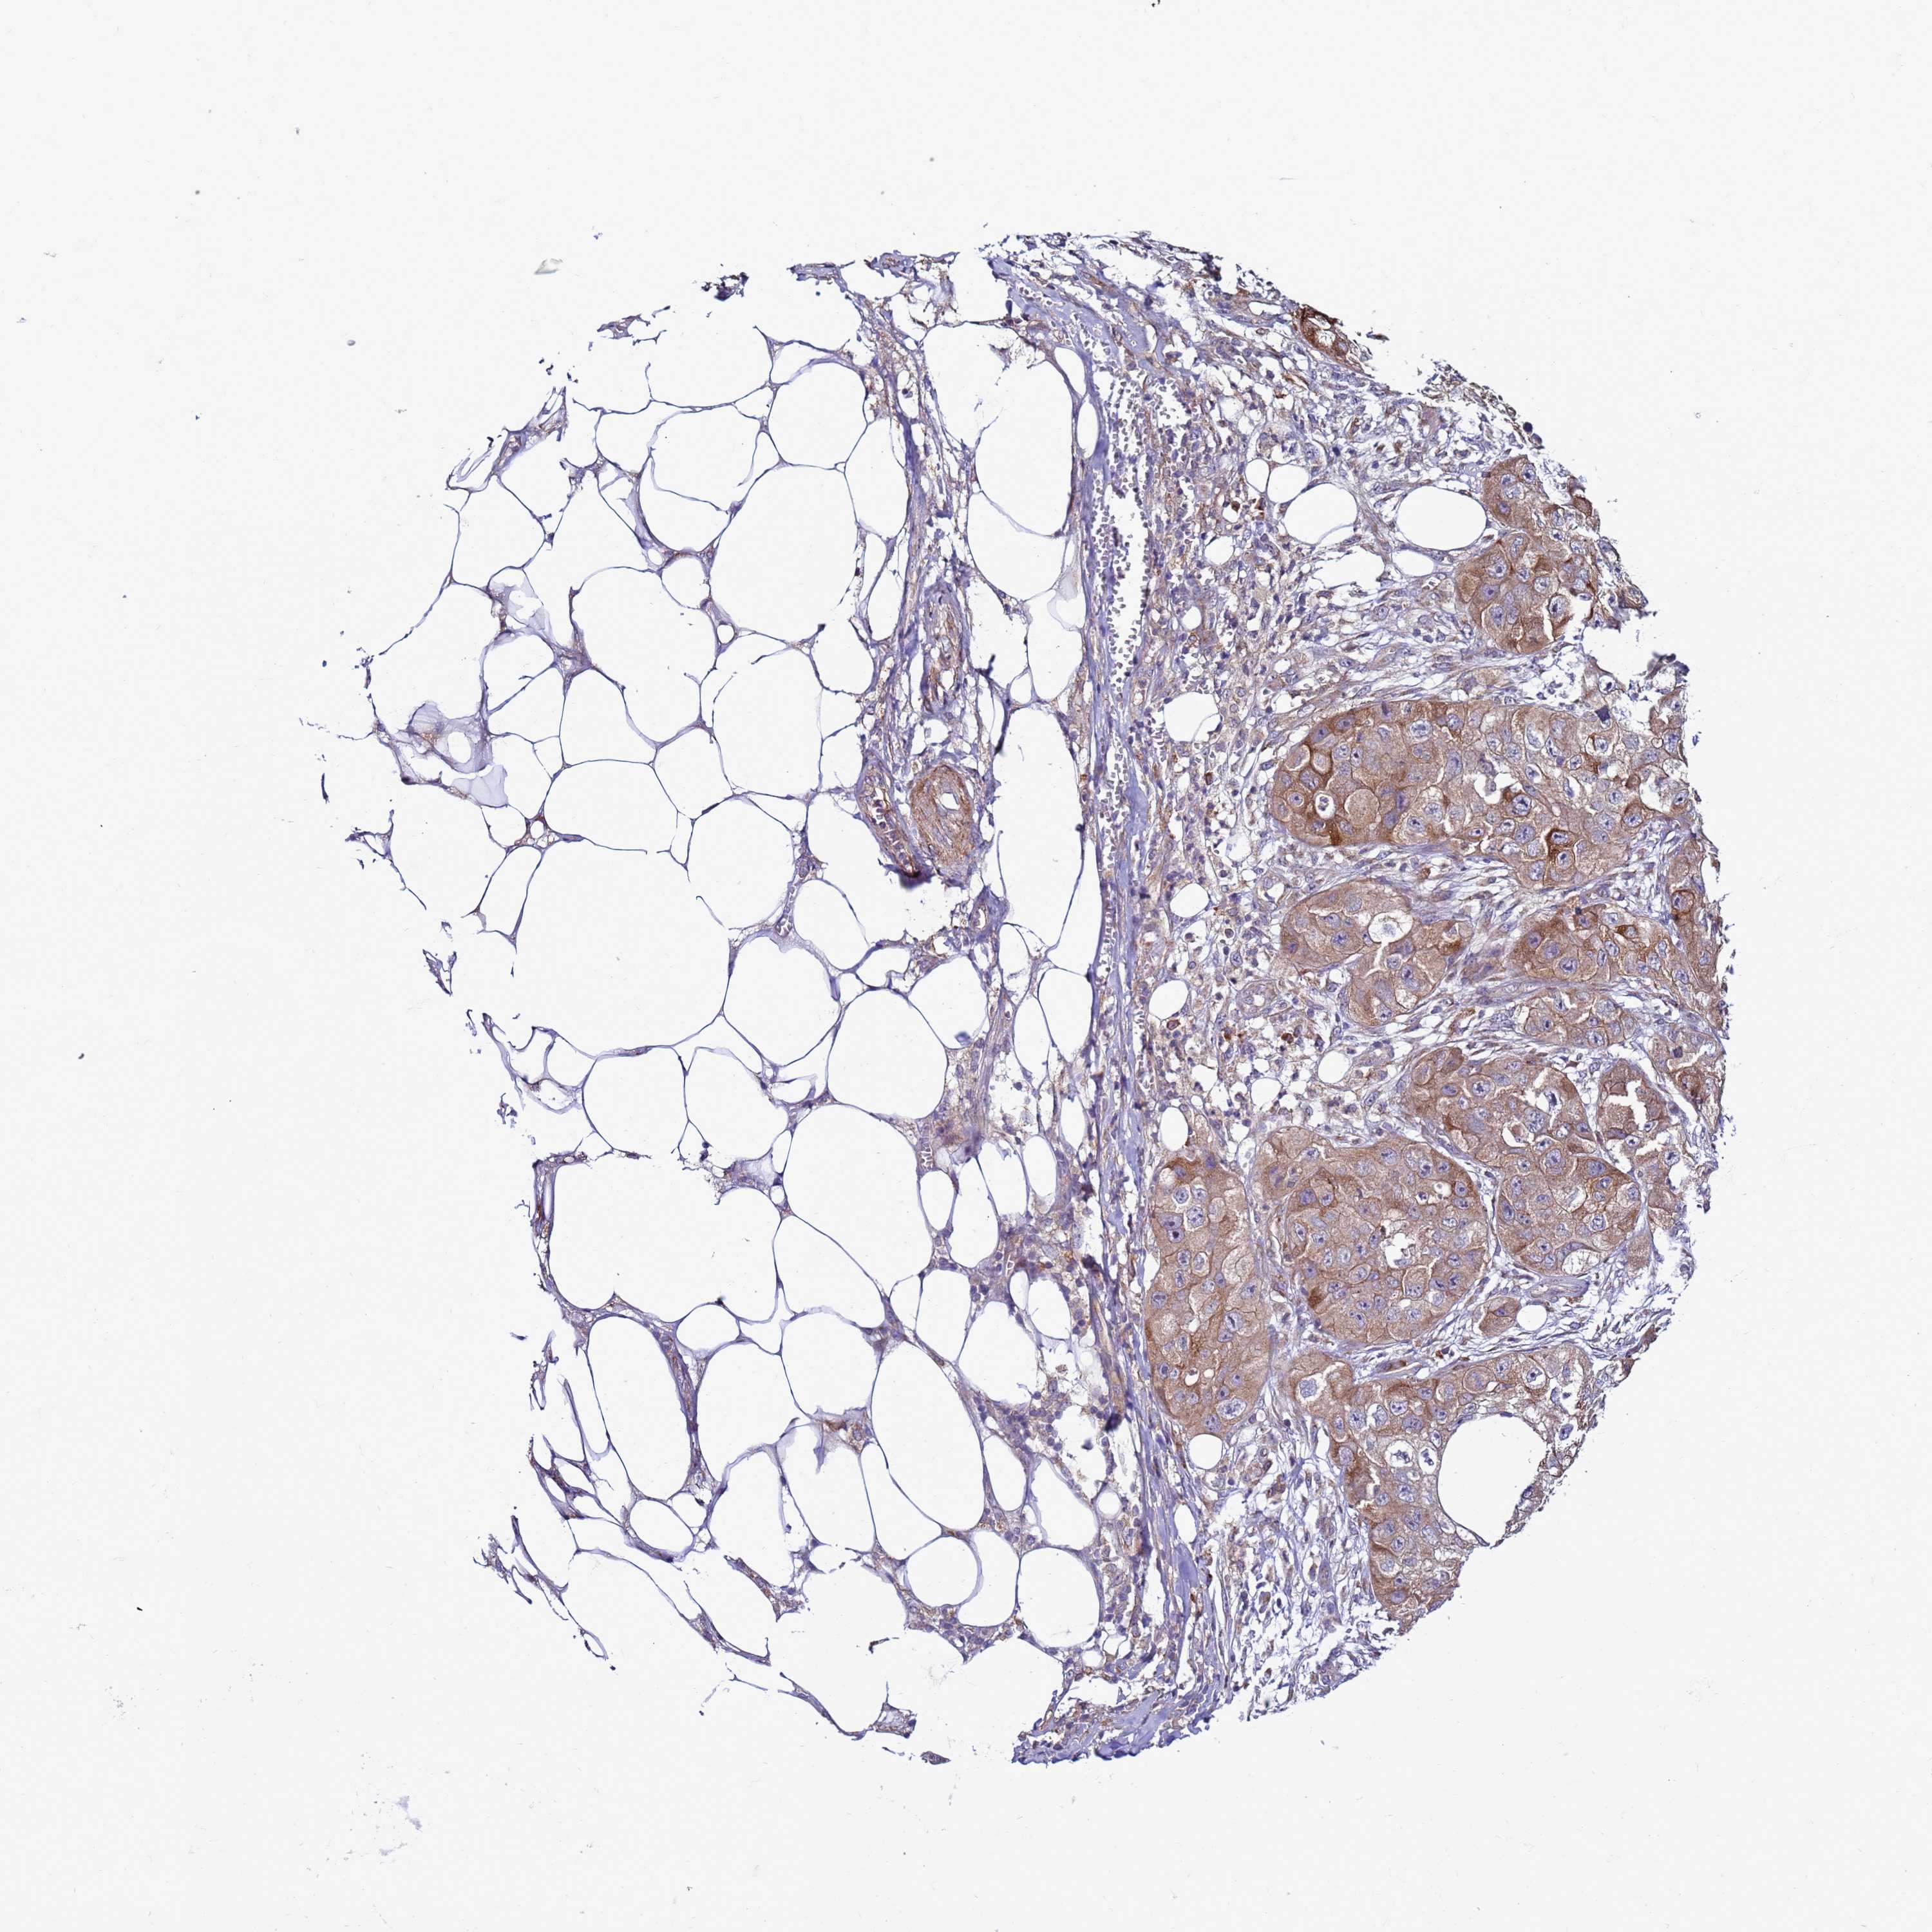

SKIN CANCER - Protein expressioni

A mouse-over function shows sample information and annotation data. Click on an image to view it in a full screen mode. Samples can be filtered based on level of antibody staining by selecting one or several of the following categories: high, medium, low and not detected. The assay and annotation is described here.

Antibody stainingi

Antibody staining in the annotated cell types in the current human tissue is reported as not detected, low, medium, or high, based on conventional immunohistochemistry profiling in selected tissues. This score is based on the combination of the staining intensity and fraction of stained cells.

Each image is clickable and will lead to virtual microscopy that enables deeper exploration of all samples and also displays staining intensity scores, fraction scores and subcellular localization as well as patient and tissue information for each sample.

Location

Nuclear

Cytoplasmic/membranous

Cytoplasmic/membranous,nuclear